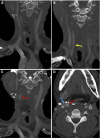

Large vessel arterial thrombosis has been reported to complicate a subset of cases of coronavirus disease 2019 (COVID-19). Thrombosis of the extracranial carotid arterial system can lead to devastating stroke in some patients with COVID-19. We have presented the case of a patient previously hospitalized with COVID-19 for oxygen supplementation who had presented after discharge with delayed stroke from a right common carotid artery and internal carotid artery thrombosis. The thrombotic occlusion resolved with antithrombotic medications and no invasive intervention. The present report highlights the complicated and heterogeneous nature of COVID-19 and provides one approach to managing the devastating complication of stroke from carotid arterial thrombosis.